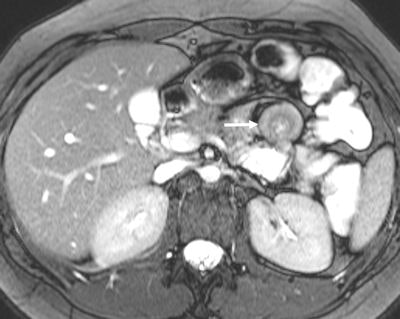

A 37-year-old female patient presented with chronic abdominal pain and was suspected of having irritable bowel syndrome. MR enteroclysis coronal fat-saturated true-FISP image demonstrates the duodenojejunal junction and proximal jejunum loops located on the right-hand side of the abdomen (arrowhead) and the normal position of the ascending colon (AC) and descending colon (DC). All images courtesy of Dr. Giedre Kavaliauskiene.There seems to be no major differences in accuracy between ultrasound, CT, scintigraphy and MRI in diagnosing inflammatory bowel disease, so it is wise to use a noninvasive technique without radiation exposure to detect small bowel lesions in patients with Crohn's disease, wrote Kavaliauskiene in an article published online on 13 July by Insights into Imaging. Important advantages of MRI are the unrestricted overview, easy comparison between examinations, and improved communication of results to the referring physician. Therefore, MRI is the technique of choice in many centers.